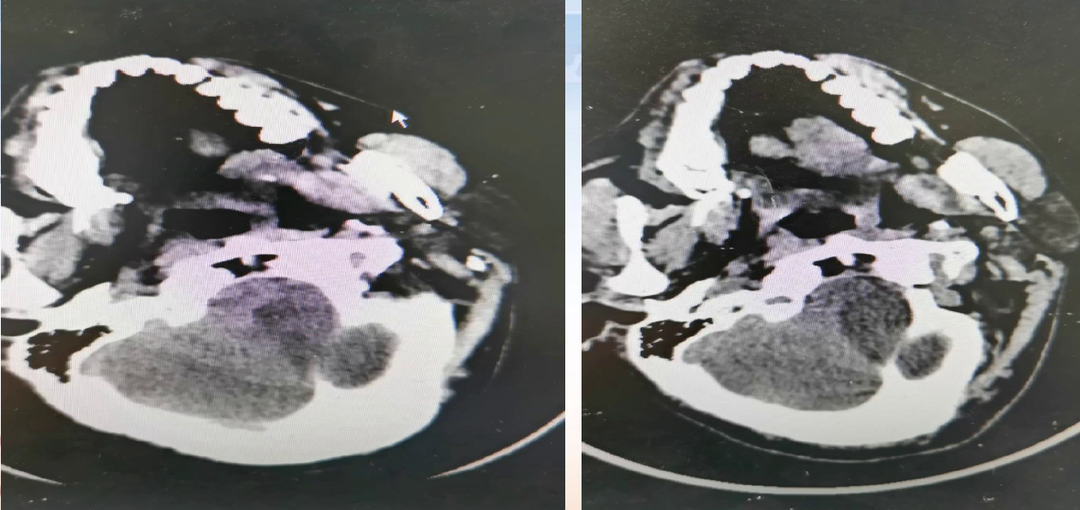

影像诊断

入院CT

病历夹什么径技·第152期|串联营病历夹:川陕大营_https://www.jmylbn.com_新闻资讯_第57张

病历夹什么径技·第152期|串联营病历夹:川陕大营_https://www.jmylbn.com_新闻资讯_第58张

术前检查

病历夹什么径技·第152期|串联营病历夹:川陕大营_https://www.jmylbn.com_新闻资讯_第59张

病历夹什么径技·第152期|串联营病历夹:川陕大营_https://www.jmylbn.com_新闻资讯_第60张

病历夹什么径技·第152期|串联营病历夹:川陕大营_https://www.jmylbn.com_新闻资讯_第61张

初步诊断:1.脑梗死(右)急性期2.右侧颈内动脉起始部次全闭塞3.右侧大脑中动脉M1段血栓形成